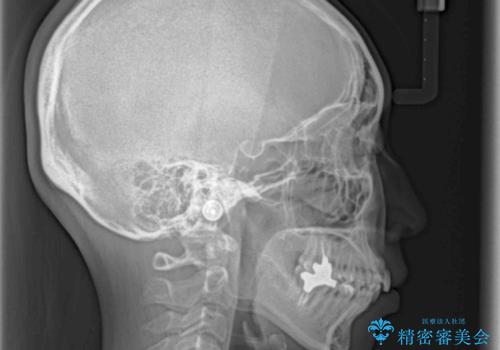

- 前歯のデコボコを気にして来院された患者様です。

非抜歯矯正にて治療を行うと、仕上がりで口元が突出する可能性があったため、小臼歯抜歯での矯正治療を行うこととしました。

上顎は左右の第一小臼歯2本を、下顎は左右の第二小臼歯2本を抜歯して、口元が突出しないようにしながら、奥歯の咬み合わせを改善していく治療計画としました。

目立たない装置が希望であったため、上顎が裏側装置である、ハーフリンガル装置を選択されました。

第二小臼歯抜歯としたため、治療期間は長くなりましたが、満足のいく仕上がりとなりました。